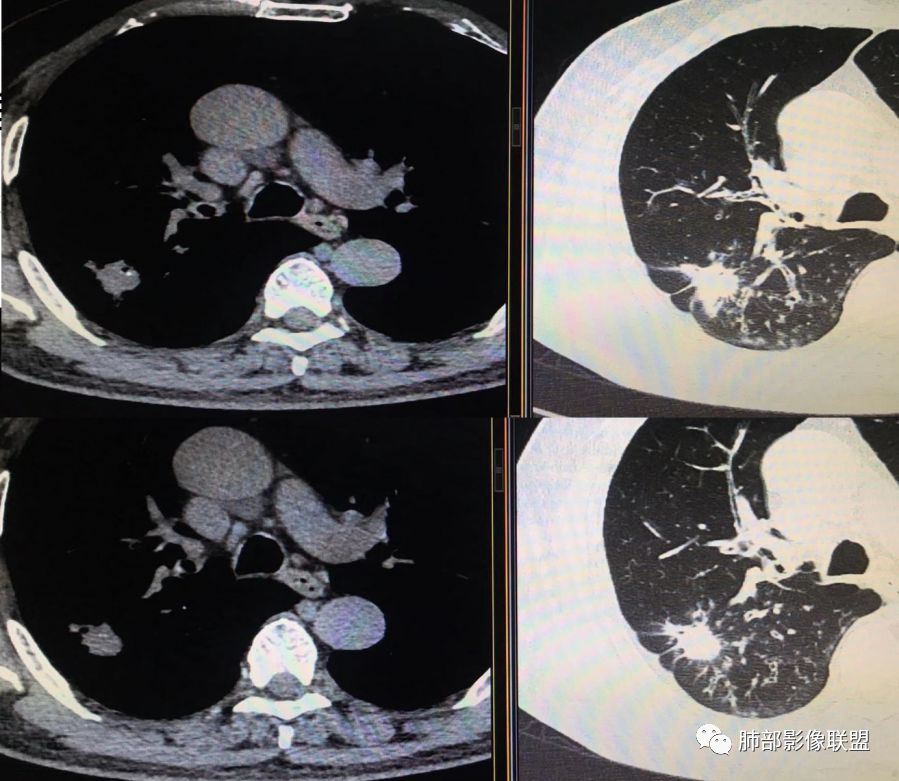

胸CT示病变位于右肺上叶,右肺上叶前段支气管壁不规则增厚狭窄、远端扩张。右肺上叶后段实变影,纵隔窗实变内可见钙化灶,可见支气管引流征,引流支气管壁明显增厚,边缘可见短硬毛刺,胸膜牵拉,u型征,周围可见卫星灶,并可见支气管扩张及其管壁增厚;病灶整体存在膨胀性生长。考虑良性病(结核)变基础上合并癌变,腺癌?

患者中老年男性,咳嗽喘息半年。查体双肺闻及哮鸣音。胸部CT:右肺上叶后段不规则结节灶,可见长毛刺、胸膜牵拉、分叶及钙化征象,周围见点片状卫星灶,近端支气管壁增厚,呈支气管爬行征。综合考虑结核。鉴别恶性病变。

右上肺的占位,毛刺,凹陷,总体偏恶性,但周围卫星灶,考虑腺癌可能性最大,结核也不能排除。

老年男性,咳嗽半年,右肺上叶后段实性结节伴粟粒状卫星灶,结节内有钙化,部分边缘平直,周围见长索条,有胸膜牵拉,结核是明确的,常规需要增强判断有无合并肺癌,当然该患者已经穿刺。

右肺上叶后段结节,点状钙化,边缘见细长毛刺,胸膜凹陷,卫星灶伴树芽症,支气管壁增厚扩张,有截断,考虑结核,但腺癌没法排除,确实有增强就基本能明确。

右肺上叶后段实性结节伴卫星灶,结节内有钙化,部分边缘平直,长索条,胸膜牵拉,考虑结核,但恶性征象还是有的,需除外腺癌!

右肺上叶后段不规则结节,长毛刺,卫星灶,斑点状钙化伴细小钙化,边缘部分平直,收缩力不强,倾向一元解释TB可能大,鉴别腺癌

右肺上叶病灶,可见分叶、毛刺、胸膜牵拉,周围见花花草草,似乎是卫星灶,考虑结核,鉴别腺癌。右肺支气管管壁增厚并扩张,考虑支扩,病史有喘息,哮鸣音,考虑合并有曲霉菌感染。综合考虑腺癌合并结核,曲霉感染。二元。

右肺上叶后段结节,长毛刺、钙化灶、近端小空洞、索条影、周围支气管树丫、引流支气管增厚,主体病灶侧后方分隔样空腔,弥漫支气管增厚,大气道受累,支持感染的征象较多,TB、曲霉;分叶、膨隆、脊状凸起、毛刺等恶性征象也有,遗憾没看到增强,只有期待活检一槌定音。

右肺上叶后段结节,呈不规则状,内可见钙化,边缘可见长短不一毛刺及胸膜牵拉,并可见分叶,邻近支气管管壁增厚,周围可见多发点状及结节状高密度影,首先考虑结核。

老年男性,咳嗽半年,右肺上叶后段实性结节,内见钙化,边缘部分膨隆,有长短毛刺、分叶、空泡征,胸膜侧见胸膜牵拉,周围不干净,见小卫星灶,右上叶后段支气管管壁增厚,扩张,有炎性及恶性征象,一元论常规考虑炎性肉芽肿病变,结核可能,腺癌不除外,二元结核并腺癌,建议增强及穿刺活检。

右上肺后段结节,边界清晰,可见分叶及毛刺,血管集束征,胸膜牵拉,内见斑点状钙化,周围见斑点状模糊影,同时伴支气管扩张,管壁增厚。整体感觉恶性征象多于良性,首先考虑肺癌,鉴别肉芽肿性病变,结核位置不像。

右肺上叶后段占位,毛刺,胸膜凹陷,病灶边缘内可见钙化、空泡,血管进入,病灶周围可见多发粟粒及树芽征,首先考虑肺结核;鉴别腺癌?鳞癌(周围小花、小草?)?

右上叶结节,毛刺、胸膜兔儿、空泡、钙化、血管,恶性征象不少,但是,可见沿支气管血管束分布的,周围可见卫星病灶,支气管扩张,外边胸膜是增厚的,结核可能性大。

中年男性,CT提示右肺上叶后段可见一结节影,可见长、短毛刺,胸膜牵拉,邻近支气管壁增厚,可见卫星灶,病灶内可见钙化,符合结核改变,腺癌待排。

右肺上叶后段团块影,内见钙化,周围胸膜有牵拉,近段支气管扩张管壁增厚,周围可见卫星灶,右支气管狭窄,综合考虑支气管内膜结核,鉴别真菌感染(气道侵袭性曲霉菌病)。

中老年男性,右肺上叶不规则团块状病灶,深分叶、长软毛刺,内部见空泡、多发钙化,相邻支气管增厚,考虑病变来源于气道,首先考虑结核,有空泡,这个腺癌多见,需要鉴别。

右肺上叶后段不规则结节,可见多发长毛刺,边界欠清,密度不均匀,其内可见斑点状钙化影,相应支气管壁增厚,管腔通畅,病灶周围见斑片状、斑点状稍高密度模糊影,考虑结核可能性较大。

中老年男性,右肺上叶不规则团块状病灶,深分叶、长毛刺,内部见空洞(近心侧)、钙化,相邻支气管增厚,有结核背景,首先考虑结核,腺癌需要鉴别。

右肺肿块,边缘平直,往下部分有膨胀感,毛刺、胸膜牵拉,内钙化,周围树芽,边界清,支气管壁增厚,考虑结核;不除外合并恶性。

右上后段结节,整体收缩,长软毛刺丶胸膜凹陷,有点状钙化丶小空洞,引流支气管明显管壁增厚,周边卫星灶明显,有喘息史半年,可能有应用激素史,致内源性复发,考虑TB,鉴别腺癌。

右肺上叶后段占位,分叶,毛刺,胸膜凹陷,病灶边缘内可见钙化、空泡,血管进入,病灶周围卫星灶,考虑肺结核合并肺癌。

不给增强图像,仅就形态判断,腺癌、结核都有可能。腺癌:分叶,毛刺,胸膜牵拉,近端支气管爬行结核:分叶,毛刺,胸膜牵拉,粗颗粒钙化散在分布,引流方向支气管壁增厚。这种情况通常放射科诊断不下结论:部位,病变,建议增强检查/穿刺活检。

这个病灶确实有点担忧局部边缘是膨隆的,结果腺癌,可能是结核合并了腺癌。

钙化与软组织成分明显不成比例时一定要小心ca,尤其钙化位于偏心的位置时,肿瘤包裹钙化。

南边:结核一定要下,癌肯定不能排除,不能排除的原因:粗短毛刺、膨隆。

(右肺肿物穿刺)肺腺癌,贴壁生长型为主,少部分为腺泡型。

3.本例病灶影像表现为:右肺上叶后段不规则结节灶,病灶整体存在膨胀性生长,可见毛刺、胸膜牵拉、分叶及钙化征象,近心端小空洞,周围见点片状卫星灶并出现磨玻璃影,近端支气管壁增厚,管腔扩张,既有恶性征象,也有结核的征象。南边老师考虑结核与腺癌同时存在,但遗憾的是缺乏增强扫描图像,亦未提供结核相关辅助检查结果。